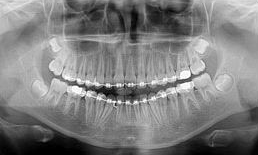

Panoramica Dentale

Lo studio radiografico delle arcate dentali fornisce informazioni fondamentali per la corretta diagnosi e formulazione dei piani di trattamento. La disponibilità diretta della strumentazione permetterà al paziente di ottenere in tempi rapidi un quadro completo dello stato di salute orale e delle cure da affrontare.